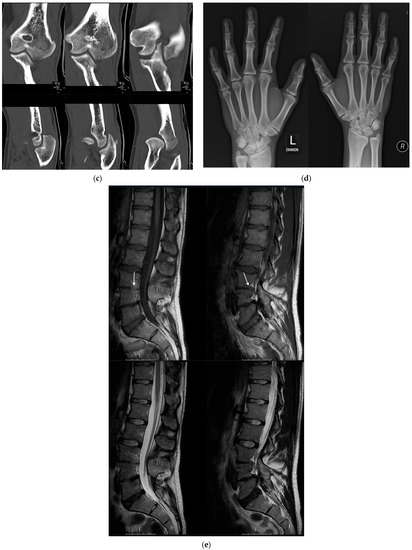

His dizygotic twin brother (patient VI.2.) presented with a slightly limited range of motion of the elbow joints. Pronation was limited by 10°, and extension of the elbow was limited by 30° (Ext/Flex 0-30-140). The range of motion of his thumbs also appeared to be slightly limited. His halluces were broad and showed valgus deviation (Figure 3a). In childhood, a bilateral hallux valgus deformity was surgically corrected; and in adolescence, a calcaneonavicular coalition was surgically corrected on both feet. He also has pectus carinatum and bilateral absence of skin creases over the distal interphalangeal joints, and he reported lumbar back pain.

Figure 3.

Patient VI.2. (a) Photograph of his feet after surgical correction of hallux valgus: note the broad and still valgus deviated halluces and sandal gaps. (b) The radiographs of the left elbow showed a dysplastic distal humerus with a tiny trochlea and dysplastic olecranon and a dysplastic convex radial head. (c) A computed tomography of the elbow depicted the malformation (upper row: coronal view, lower row: sagittal view). (d) Radiographs of the hands displayed a dysplastic first metacarpal base and head, flattening of the heads of metacarpal 3 and 4 as well as synostosis of the middle and distal phalanges of the fifth fingers. (e) An MRI of the lumbar spine revealed a partial posterior vertebral synostosis marked by arrows of L3 and L4 (upper row: T1-weighted images, lower row: T2-weighted images).

Radiographs of the left elbow showed a dysplastic distal humerus with a tiny trochlea and dysplastic olecranon and a dysplastic convex radial head (Figure 3b). A computed tomography of the elbow depicted the malformation (Figure 3c). Radiographs of the hands displayed a dysplastic first metacarpal base and head, flattening of the heads of metacarpals 3 and 4 as well as synostosis of the middle and distal phalanges of the fifth fingers (Figure 3d). The radiographs of the feet before correction of the calcaneonavicular coalition displayed a coalition between the anterior processus calcanei and the os naviculare. An MRI of the spine showed partial lumbar vertebral synostosis L3-L4 (Figure 3e).